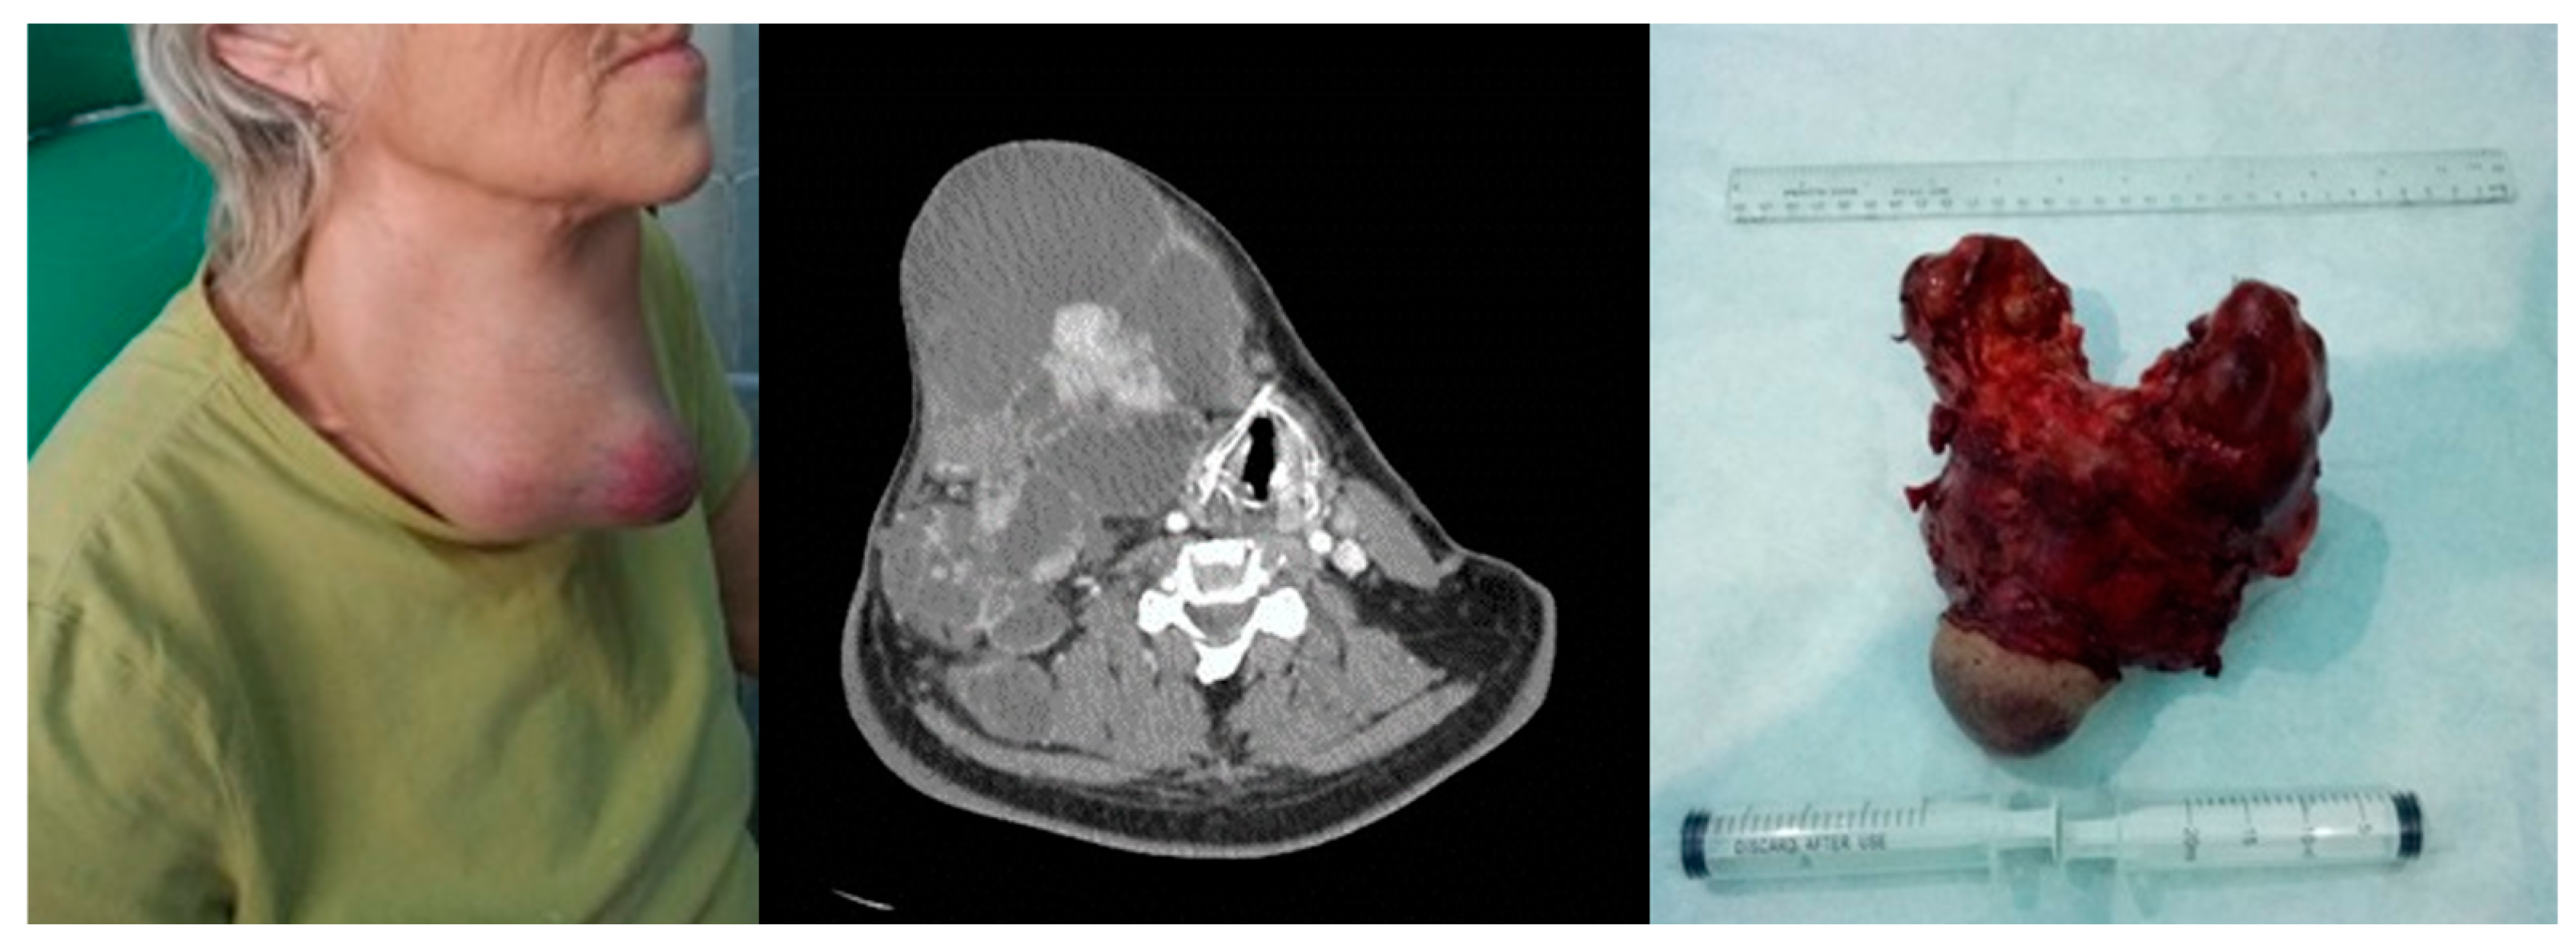

Breakdown by evolution: the LTS giant follicular cyst case was followed at 1 month and 3 months and then endocrinologically discharged, and the five poly nodular goiter follicular adenoma cases were followed at 1 month and 6 months and entered in the endocrinological dispensary. Among the 21 cases of the studied group, there were 16 survivors at 5 years, in oncological monitoring at 3 months. The four cases of anaplastic carcinoma resulted in death, as well as one case of papillary carcinoma with multiple metastatic disease. The outcome was through tracheal invasion—four cases, respectively, through multiple metastatic disease—one case. Among the four cases of anaplastic carcinoma, three cases followed chemotherapy, with resumption of evolution and exitus, respectively, and one case had a resumption of evolution 6 weeks postoperatively, with exitus, Figure 5.

Anaplastic thyroid carcinoma. Left image—clinical aspect. Center image—axial CT scan with tumor displacement of the airway. Right image—resection piece 750 g.